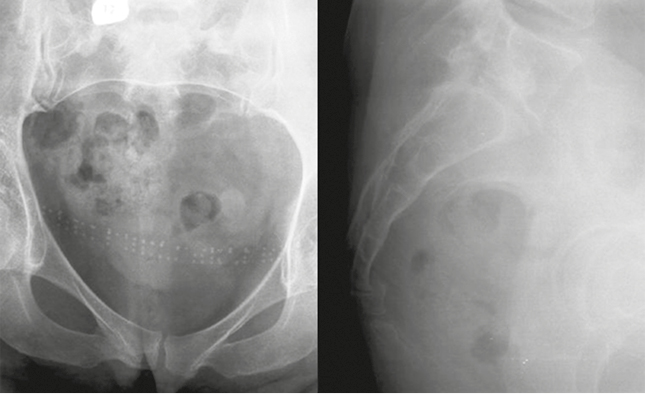

Второе клиническое наблюдение. Пациентка Б., 39 лет, находилась на лечении в клинике военной травматологии и ортопедии Военно-медицинской академии им. С.М. Кирова в июне 2019 г. Травму копчика получила 16 месяцев назад, катаясь на «ватрушке». Получала длительное консервативное лечение по поводу кокцигодинии (физиотерапия, анальгетики, блокады) с временным эффектом. По данным лучевого исследования выявлен застарелый подвывих копчика кзади и наличие костной «спикулы», спонтанный «костный блок» на уровне крестцово-копчикового сочленения (рис. 4). При ректальном исследовании обнаружена значительная подвижность копчика, сопровождающаяся выраженной болью. В клинике больной выполнена резекция копчика, послеоперационное течение без осложнений (рис. 5–8). Пациентка выписана на 4-е сутки после операции. Индекс ВАШ через 1 месяц после операции составил 2 балла, а при дальнейшем наблюдении — 1 балл. По шкале удовлетворенности операцией — «полностью удовлетворена».

Рис. 4. Компьютерная томография крестца и копчика пациентки Б. до операции

Fig. 4. CT of the sacrum and coccyx of patient B. before surgery